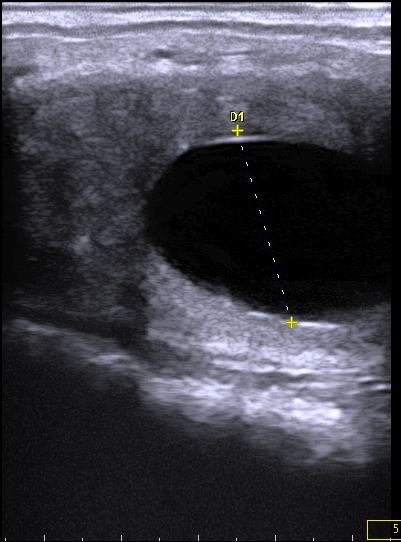

Die Ultraschalluntersuchung (Sonographie) ist das Mittel der Wahl zur Untersuchung von Weichteilgewebe (Muskulatur, Sehnen, Gelenkkapseln, Körperorgane u. a.). Wir setzen die Ultraschalluntersuchung in der Orthopädie, Gynäkologie, Inneren Medizin, bei Augen- und Fohlenerkrankungen ein.

In der Orthopädie ist der Ultraschall in hochauflösender Darstellung ein unverzichtbares Hilfsmittel zur genauen Untersuchung und Quantifizierung von Schäden an Sehnen, Bändern und Gelenken. Die Zyklus- und Trächtigkeitsdiagnostik im Rahmen der Gynäkologie wird durch die Sonographie spezifiziert und optimiert. In der Inneren Medizin kommt zur Untersuchung der Bauchhöhle und Bauchhöhlenorgane (z. B. Darm, Magen, Niere, Blase, Leber) ein Ultraschallgerät mit größerer Eindringtiefe zum Einsatz. Bei der Augenuntersuchung ist die Sonographie ein wichtiges Hilfsmittel zur Beurteilung der hinteren Augenabschnitte. Der Nabel und die Bauchhöhle des Fohlens können gut mittels Sonographie auf krankhafte Veränderungen untersucht werden.